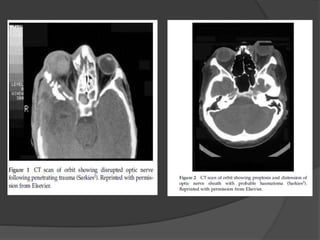

DIRECT INJURIES

 Result from objects that penetrate the

orbit and impinge on the optic nerve

causing optic neuropathy by partial or

complete transection of the optic

nerve sheath. Hemorrhages within and

around the nerve may also occur